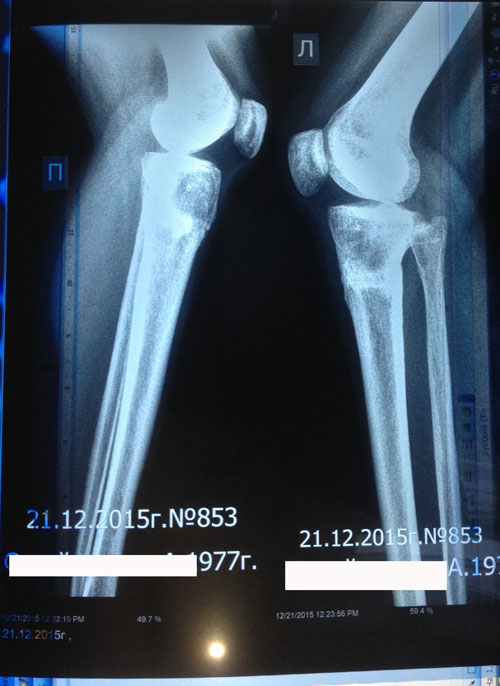

1,5 месяца с момента снятия аппаратов.

Здравствуйте, aneka2014! Всё отлично, сращение железное! Примеряйте каблуки любой высоты, спорт, фитнес и всё что хотите кроме: беременности в первые 6 месяцев с момента снятия аппаратов!